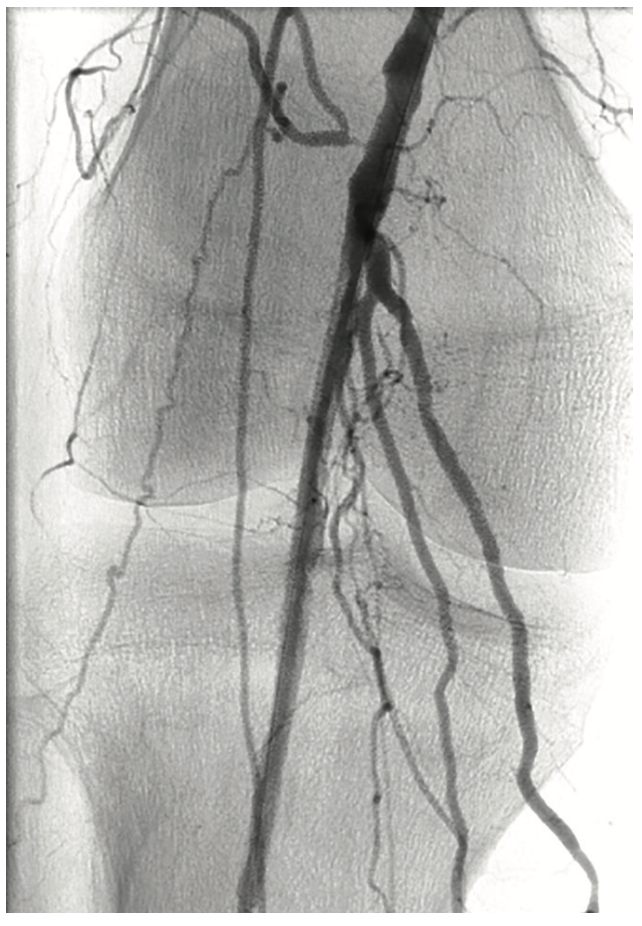

A 6 French (Fr) sheath was inserted into the right femoral artery in an antegrade fashion. An .035-inch x 90 cm Trailblazer (Medtronic) was inserted over an .035-inch x 180 cm Aquatrack guidewire (Cordis, A Cardinal Health company) and advanced into the right popliteal artery. Angiography was performed prior to surgical cut down of the posterior tibial artery (PT) (Figure 1). Access into the PT was made using a 4 Fr micropuncture pedal sheath (Cook Medical). An .014-inch Confianza guidewire (Asahi Intecc) was inserted and advanced into the PT. Using the stiff Confianza, a Viance Flexible CTO catheter (Medtronic) was advanced. When Viance extravasated from the PT, an Aquatrack wire and .035-inch Trailblazer were introduced and advanced in a antegrade manner. The Viance and Trailblazer could be visualized going in different directions (Figure 2). Using that image, the Viance was pulled back and repositioned to find the true lumen from the bottom to the top, using the guidance from the wire. The Confianza was readvanced after the true lumen was found, and Aquatrack was pulled back into the Trailblazer and eventually removed. The Confianza wire was advanced further into the .035-inch Trailblazer, and eventually pulled through the right femoral artery sheath in a retrograde fashion (Figure 3). The right femoral artery Trailblazer was removed. A TurboHawk SX-C atherectomy catheter (Medtronic) was used to debulk the plaque and achieve luminal gain from the popliteal artery into the tibioperoneal trunk (Figure 4). Drug-coated balloon angioplasty was performed using the IN.PACT balloon (Medtronic) into the popliteal artery (Figure 5). The TurboHawk was reinserted and advanced further down to the peroneal artery into the tibioperoneal trunk in order to establish luminal gain in the distal vessel. Final angiography revealed successful recanalization of the lower extremity vessels through the use of the antegrade/retrograde method, with distal access through the posterior tibial artery (Figure 6).